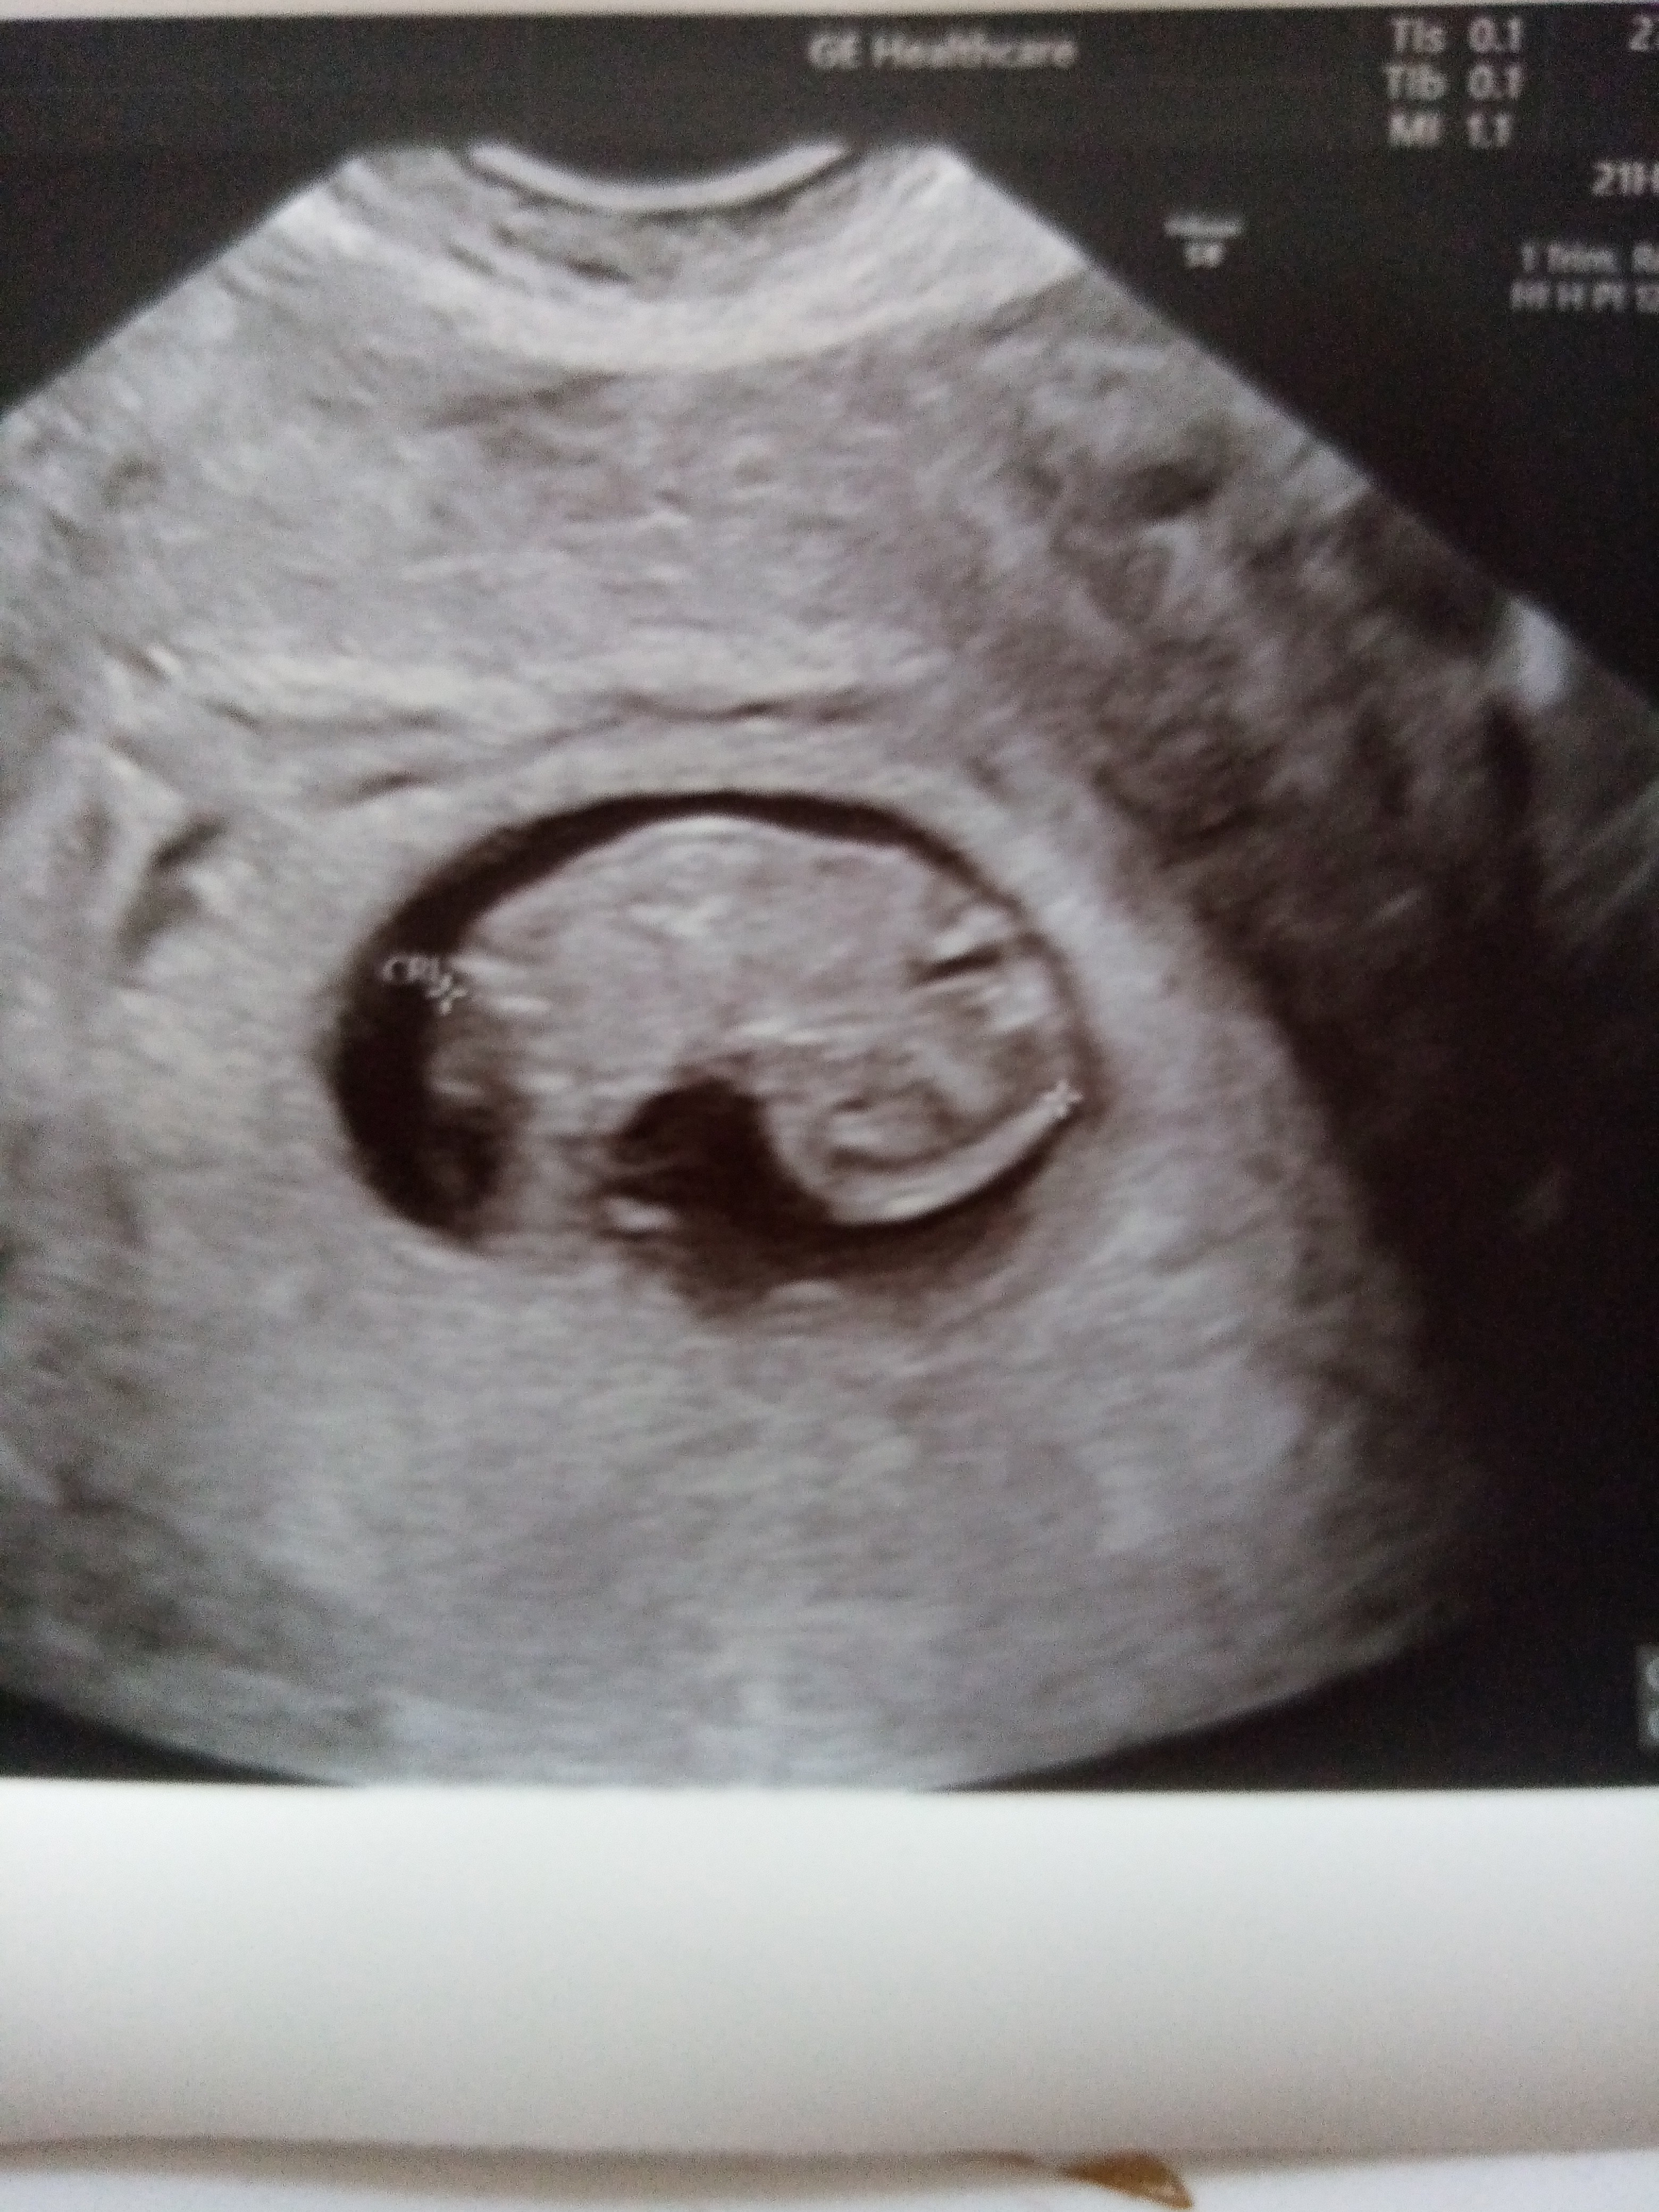

Ja dziś po wizycie. Dzidzia rozwija się wzorcowo, serduszko bije.Aktualnie 8+5.

Termin przewidywany jak z OM czyli otwieram rok😊01.01. Kolejna wizyta za 2 tyg.

IMG_20230527_104328.jpg